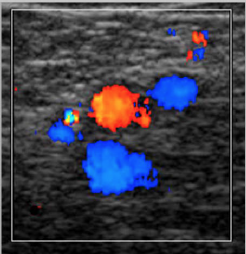

color

Spectral to show: Spontaneous flow, Cessation of flow with proximal compression or valsalva and Optional: augmentation of flow with distal compression

Color with distal augmentation to fill vessels at mid calf. Demonstrate: Posterior tibial, Peroneal

Color should fill vessel. Flow toward head

Helps demonstrate partial thrombus

Helps identify vessel

Doppler instrumentations: 60 degree angle or less

Low scale – artery will likely demonstrate aliasing, that’s okay. Low filter. Gain up high enough

Color Doppler Energy (Power) may help